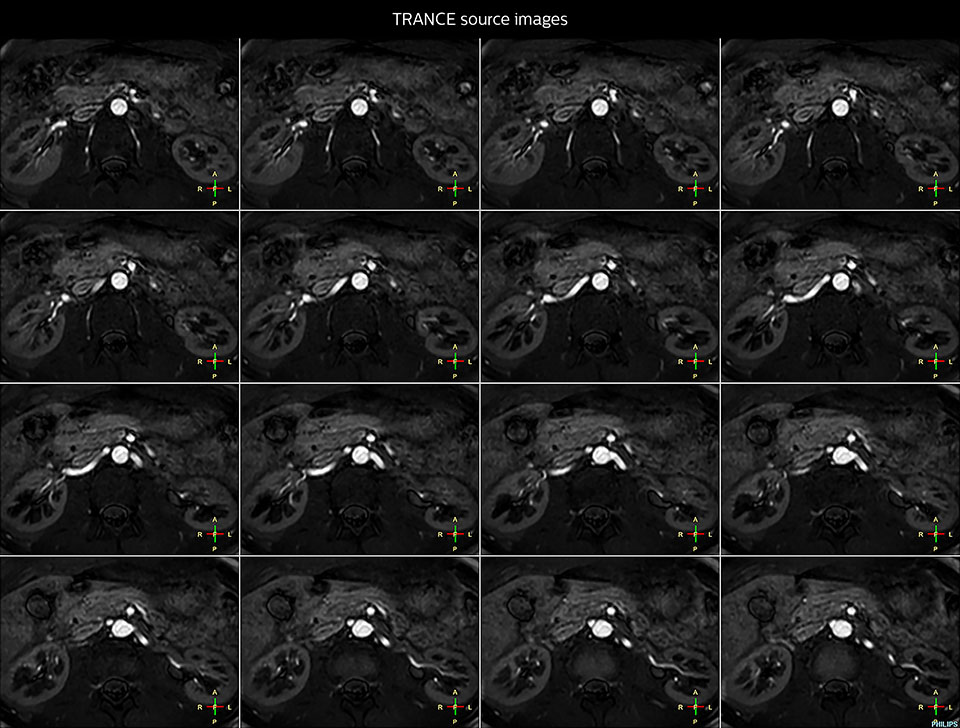

Bildgebung der Nierenarterien ohne Kontrastmittel mit Prodiva 1.5T.